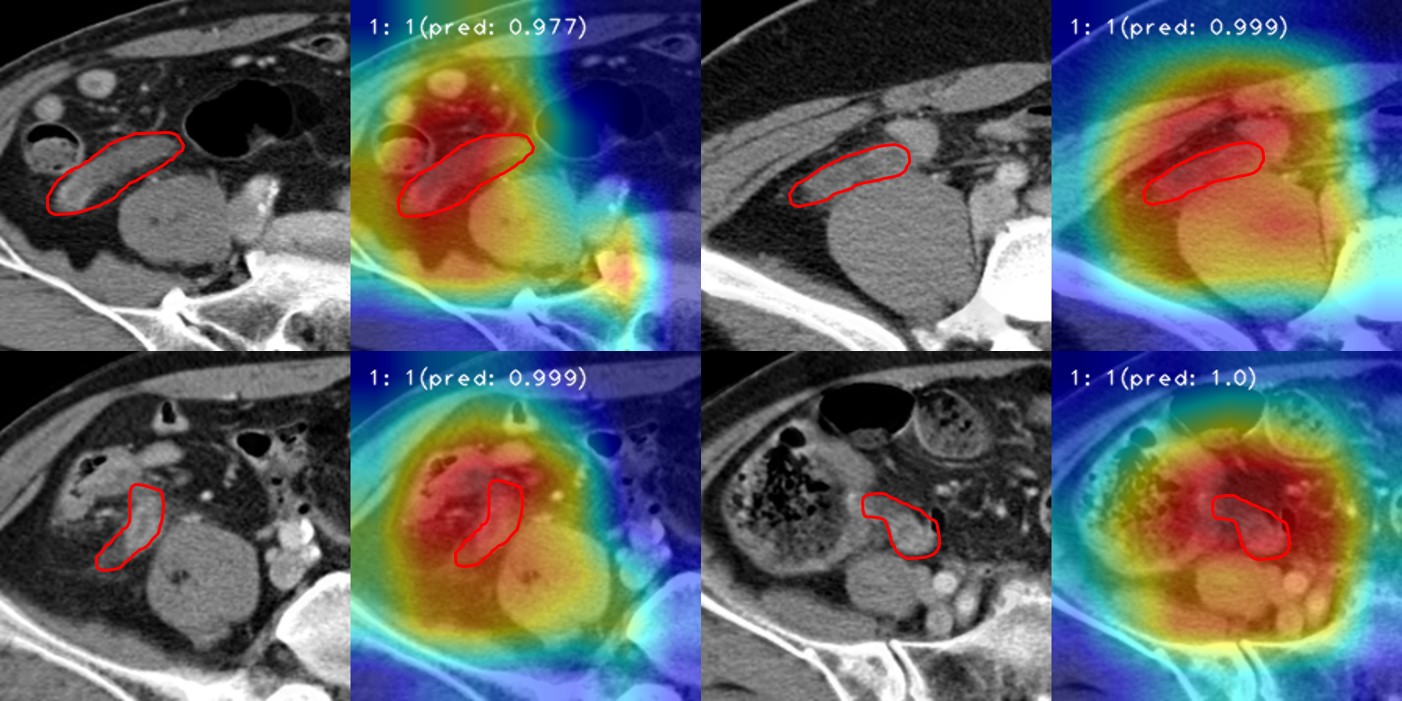

ÀÌÈÄ Ãæ¼ö¿° ȯÀÚ 1839¸í, Ãæ¼ö¿°ÀÌ ¾Æ´Ñ °ÍÀ¸·Î Áø´Ü¹ÞÀº 1782¸íÀÇ µ¥ÀÌÅ͸¦ °É·¯³»°í ¡®3D ÄÁº¼·ç¼Ç ½Å°æ¸Á(Convolutional Neural Network, CNN)¡¯À» Ȱ¿ëÇÑ ¸ðµ¨¿¡ ÇнÀ½ÃÄ×´Ù.

ÇнÀÀ» ¸¶Ä£ AI¸ðµ¨ÀÇ Ãæ¼ö¿° Áø´Ü Á¤È®µµ´Â 89.4%·Î ³ªÅ¸³µ´Ù. AI¸ðµ¨ÀÇ ¼º´ÉÀ» Æò°¡ÇÏ´Â µ¥ »ç¿ëÇÏ´Â ¡®°î¼±ÇϸéÀû(Area Under the Curve, AUC)¡¯ Á¡¼ö´Â 0.890À¸·Î ³ªÅ¸³ª ½ÇÁ¦ ÀÓ»ó¿¡ Àû¿ëÇÒ ¼ö ÀÖ´Â ¿ì¼öÇÑ °á°ú¸¦ º¸¿´´Ù.

Á¶¹üÁÖ ÀÇ·áÀΰøÁö´É¼¾ÅÍÀåÀº ¡°À̹ø AI´Â ±âÁ¸ ¸ðµ¨µé°ú ´Þ¸® 3Â÷¿ø CT¿µ»óÀ» ÀÔüÀûÀ¸·Î ÀνÄÇß´Ù´Â Á¡¿¡¼­ ÀÇÀǰ¡ ÀÖ´Ù¡±°í Çß´Ù.